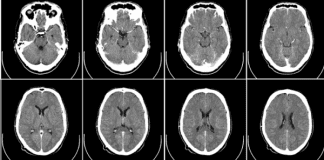

Study Rundown: Guidelines support the administration of alteplase to appropriately selected stroke patients with a time last seen well within 4.5 hours. The time of stroke onset is often unknown, as in the case of “wake-up strokes,” which excludes many patients from beneficial treatment. Previous work has demonstrated that in acute ischemic stroke, an MRI pattern of a diffusion-weighted imaging (DWI) lesion without a fluid-attenuated inversion recovery (FLAIR) lesion is predictive of the stroke happening within 4.5 hours. The investigators of this randomized controlled trial aimed to evaluate if DWI-FLAIR mismatch could select patients with stroke of unknown time that would benefit from intravenous thrombolysis. The primary endpoint was a favorable outcome at 90 days, defined as a modified Rankin scale score of 0 or 1. Patients with unknown stroke time and DWI-FLAIR mismatch who were treated with alteplase had significantly higher rates of a favorable outcome at 90 days compared to those treated with placebo. There were higher rates of death and symptomatic intracranial hemorrhage (ICH) in the treatment arm, but these associations did not reach statistical significance.

In-Depth [randomized controlled trial]: This multicenter randomized controlled trial enrolled 503 patients from 2012 to 2017 and assigned patients to alteplase (n=254) or placebo groups (n=249). The study sought to evaluate if alteplase would improve functional outcomes amongst patients with a stroke of unknown time of onset, but with a DWI-FLAIR mismatch. Key inclusion criteria included an unknown time of stroke onset and presence of a lesion on DWI but not FLAIR imaging. Important exclusion criteria included contraindications to thrombolysis, lesions larger than 1/3 the size of the middle cerebral artery territory, severe stroke defined as an NIH stroke scale score of greater than 25, and patients with a planned thrombectomy. The primary endpoint was a favorable outcome at 90 days, defined as a modified Rankin scale score of 0 or 1. Key secondary endpoints at 90 days included the ordinal score on the modified Rankin scale, quality of life scores, and MRI infarct volume at 22-36 hours after randomization. Key safety endpoints included death and symptomatic ICH.

Most patients (89%) included in the study experienced a ‘wake-up stroke’ (as opposed to confusion or aphasia confounding ascertainment of time of onset). At 90 days, the number of patients in the alteplase group who experienced a favorable outcome was 11.5% higher than in the placebo group (53.3% vs 41.8%; adjusted odds ratio, 1.61; 95% confidence interval [CI], 1.09 to 2.36; p = 0.02). The median modified Rankin score was significantly better in the alteplase group at 90 days, as was the average total score on a quality of life scale. The MRI infarct volume at 22-36 hours post-randomization was not significantly different between the two groups. The number of deaths was higher in the alteplase group (10 vs. 3 in placebo), as was the number of symptomatic ICH (2% vs. 0.4% in placebo) events, but neither association was statistically significant.